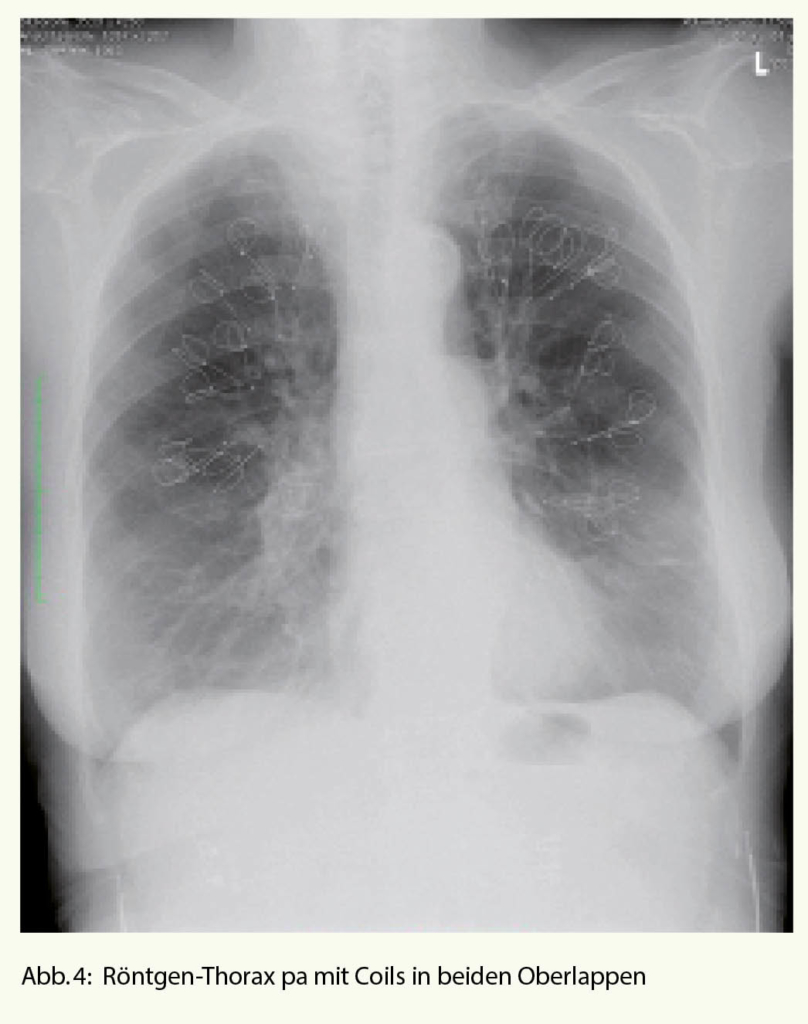

Bei den Coils handelt es sich um Drähte aus Nitinol, welche in gestrecktem Zustand über das flexible Bronchoskop in die Atemwege eingelegt werden und dort nach der Implantation ihre Spiralform wieder annehmen. Neben dem volumenvermindernden Effekt kommt es zu einer zusätzlichen Traktion an den Atemwegen (Zunahme des elastic recoil), welche durch die Coils offen gehalten werden. Insbesondere unter Belastung scheint sich diese Wirkung zu entfalten (Abnahme der dynamischen Überblähung). Es werden bis zu 12 Coils in einem Lungenlappen subsegmental implantiert. Das Vorgehen wird dann idealerweise auf der kontralateralen Seite nach 1 Monat wiederholt (Abb. 4).